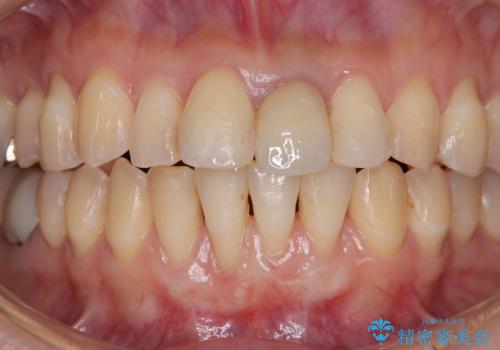

一度の処置で大幅に露出部の被覆に成功しましたが、更なる厚みと被覆を希望されて2回目の処置を行いました。

歯根部周辺の歯肉が非常に分厚くなり、今後の退縮リスクが大きく軽減されました。